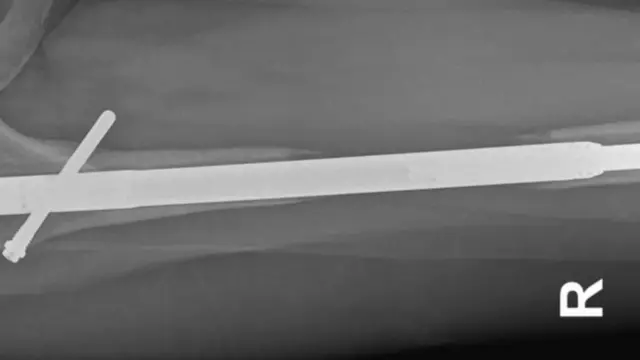

Tokom operacije, kosti nogu se slome na dva dela, a potom se ugrađuje metalna šipka-implant.

Metalne šipke se postepeno protežu i razdvajaju dva kraja slomljene kosti.

Kako se ovim zahvatom stvara prostor između dva kraja kosti, nova kost raste da popuni tu prazninu.

Šipka-implant u njenoj levoj nozi je probila butnu kost, najjaču kost u ljudskom telu.

„Doktor Giše mi je rekao da se šipka slomila dok ju je vadio", kaže ona.